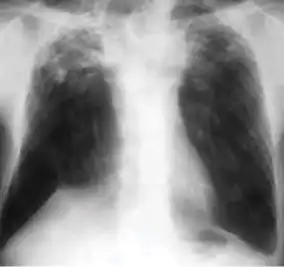

1. Infiltrate or consolidation - Opacification of airspaces within the lung parenchyma. Consolidation or infiltrate can be dense or patchy and might have irregular, ill-defined, or hazy borders.

Dense homogenous opacity in right, middle and lower lobe of primary pulmonary TB.

Chest x-ray showing patchy opacification on the upper right and mid-zone lung with fibrotic shadows, as well as bilateral hilar lymphadenopathy.